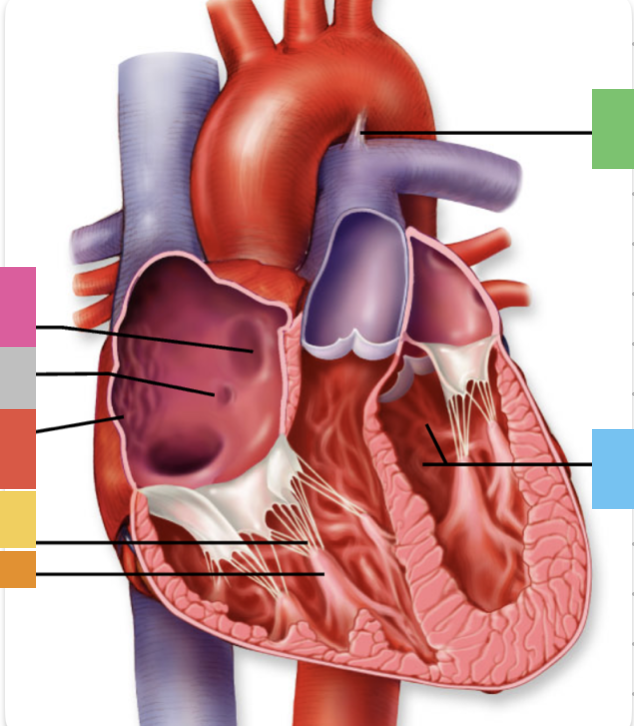

light purple

base

purple

apex

grey

right atrium

pink

right auricle

green

left atrium

green

left auricle

blue

right ventricle

orange

left ventricle

green

coronary (atrioventricular) sulcus

pink

interatrial septum

dark blue

interventricular septum

green

anterior interventricular sulcus

green

posterior interventricular sulcus

orange

aortic valve

yellow

pulmonary valve

red

tricuspid valve (right AV)

purple

bicuspid valve (left AV)

yellow

chordae tendineae

orange

papillary m.

blue

trabeculae carneae - only in ventricles

red

pectinate m. - only in R atrium

pink

fossa ovalis

grey

opening of coronary sinus